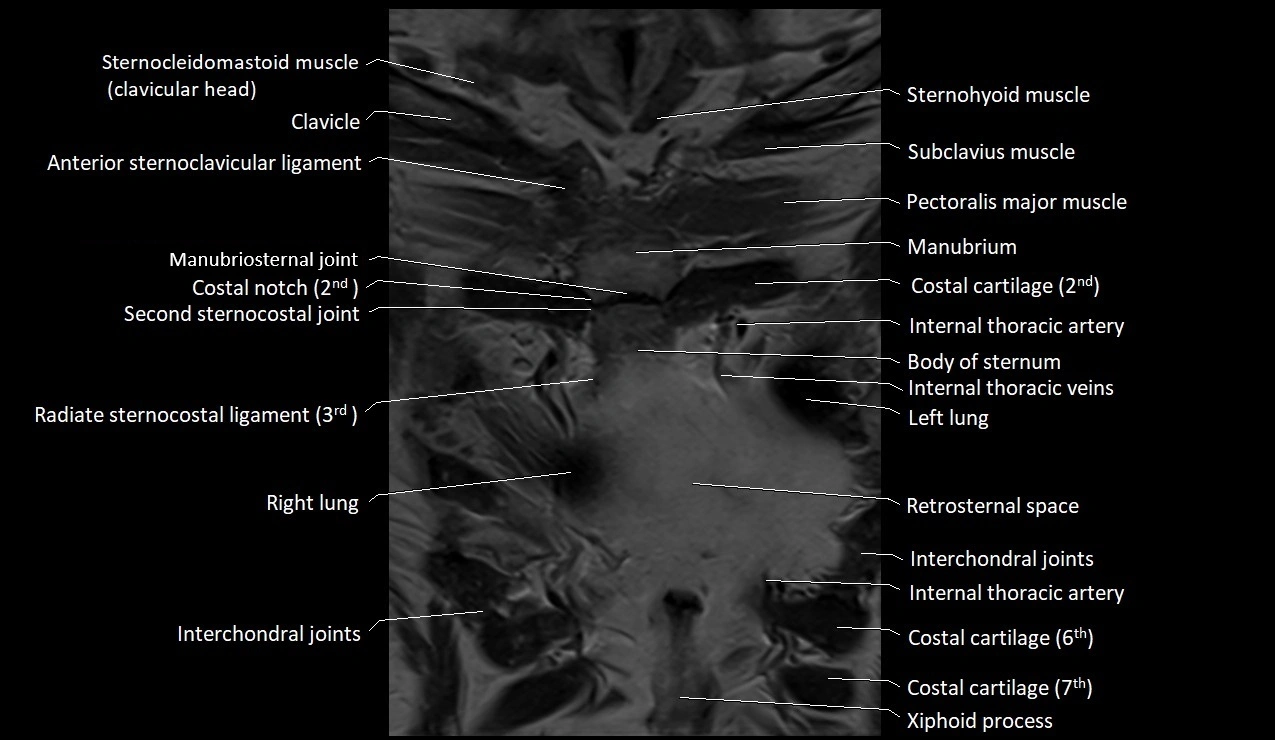

MRI images

image